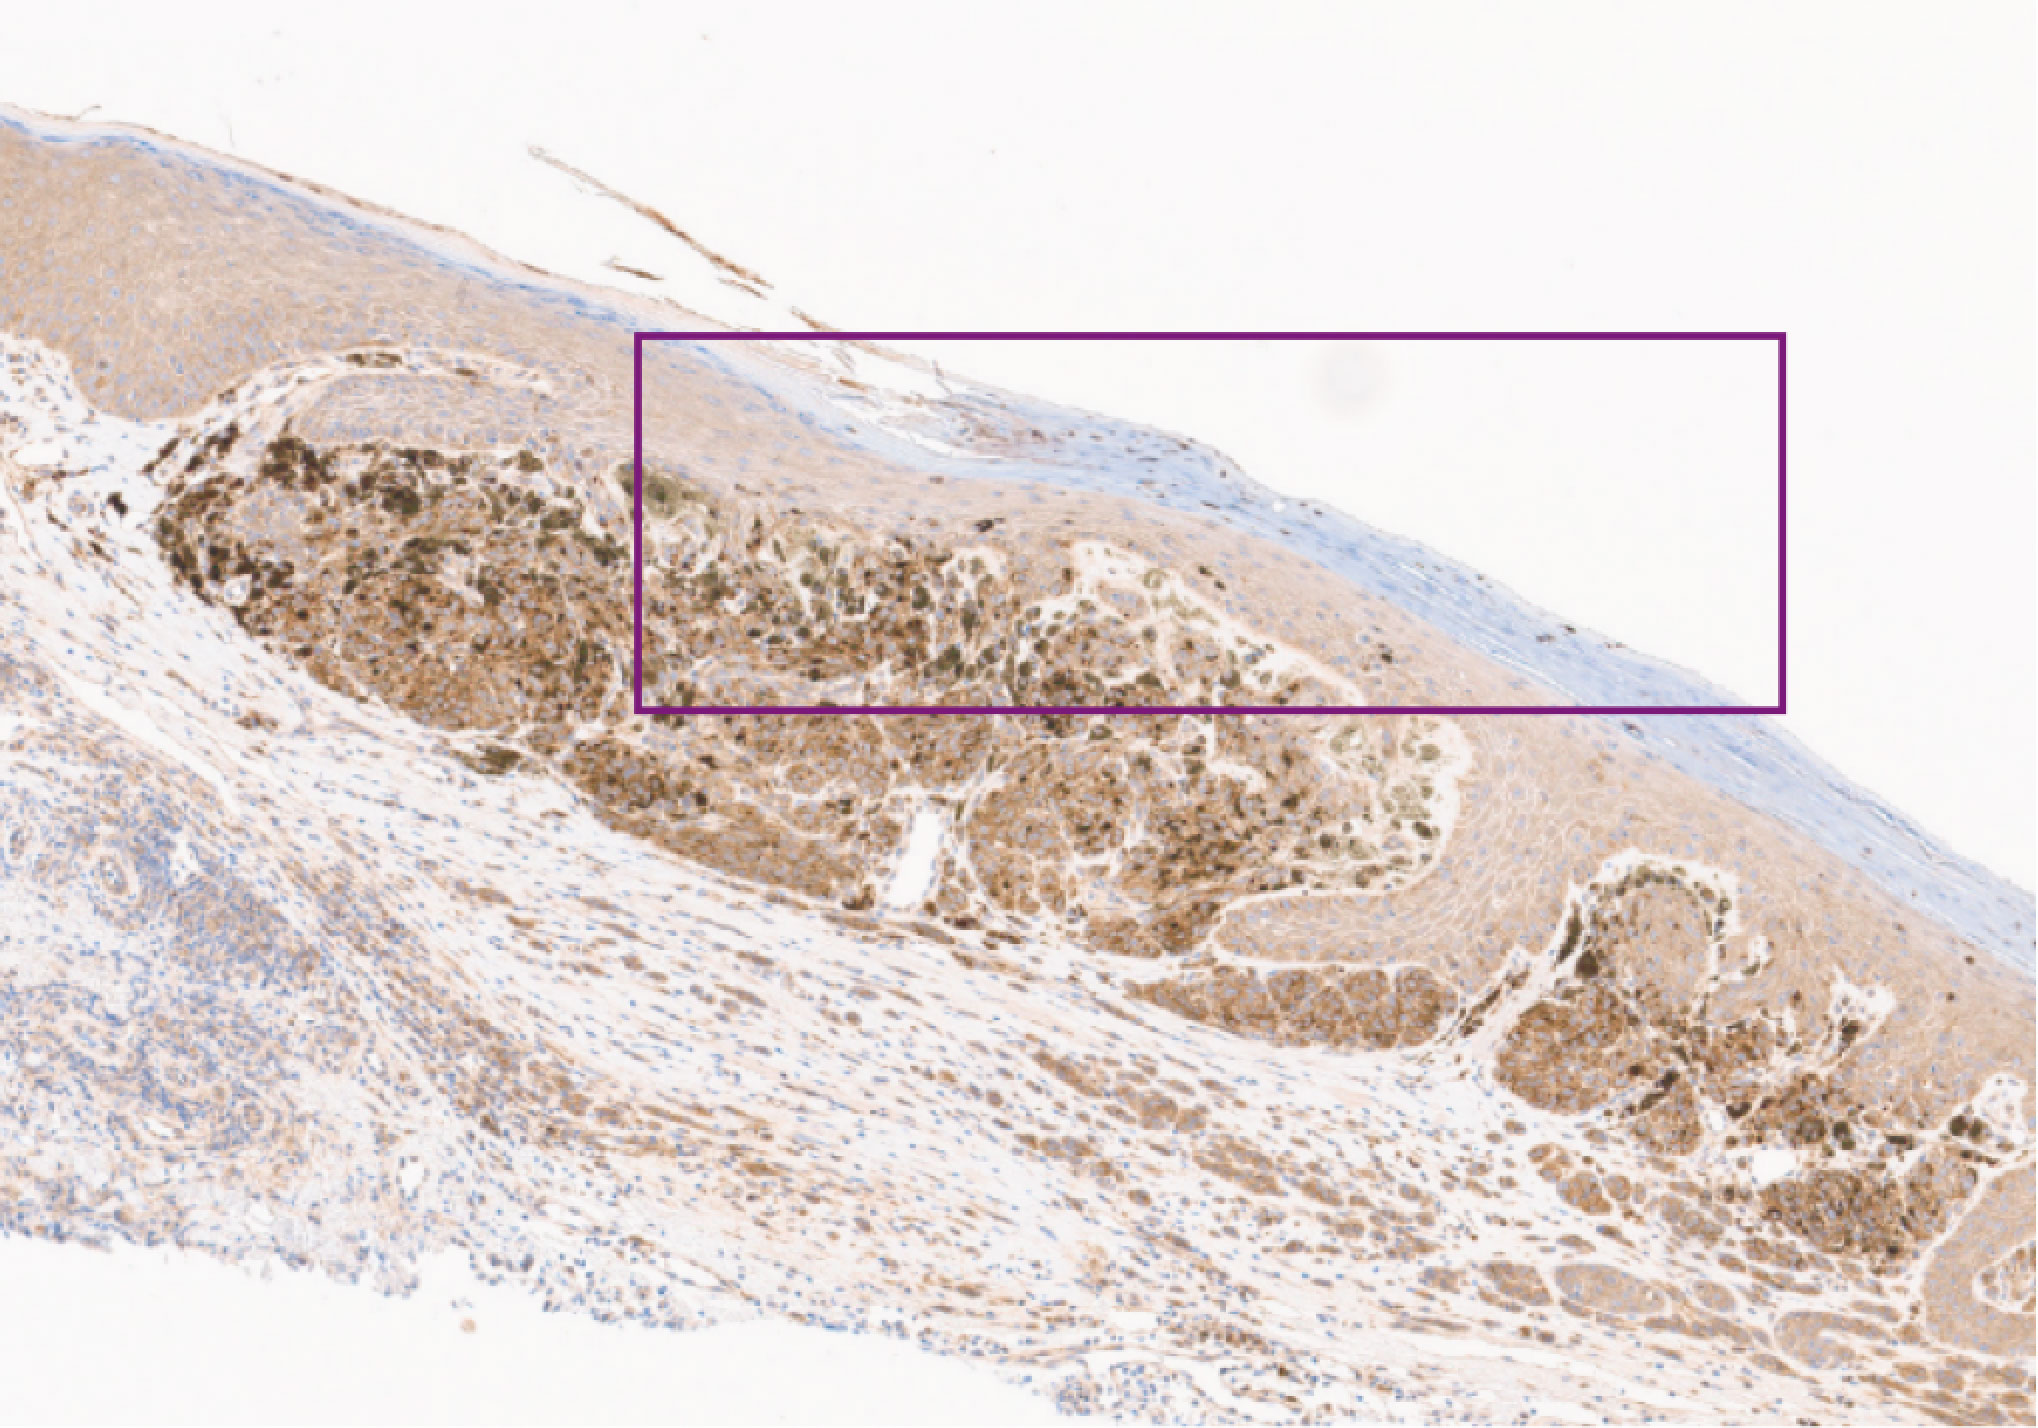

Histopathology slide – loricin lost (4x magnification)

Image 3: Loricrin Lost x4

For the patient in question, with family permission, AMBLor was performed postmortem upon recuts of the formalin fixed paraffin block of the left lateral upper back lesion. Both AMBRA1 and Loricrin were lost in this lesion, indicating that the patient’s left lateral upper back lesion was ā€œAT-RISKā€. The at-risk outcome is consistent with a level of risk of metastasis associated with current AJCC staging.